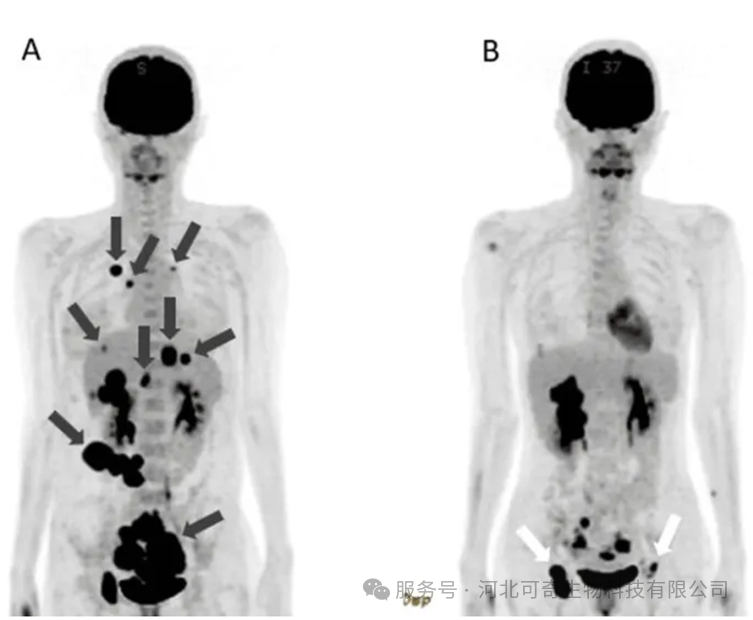

NK 细胞治疗前后腹部 CT 对比

(A)确诊时:大量腹水(*)、肝转移灶(白色箭头)清晰可见。

(B)治疗 56 天后:腹水明显减少,肝转移灶显著缩小。

随着 NK 细胞治疗的推进,患者血液中性粒细胞 / 淋巴细胞比率(N/L)持续下降,逐渐转变为淋巴细胞占优势。第 142 天 PET-CT 显示,肺转移灶与腹膜播散灶完全消失,肝转移灶及原发病灶明显缩小。治疗期间,患者仅出现注射 DC 或 NK 细胞引发的发热,无其他明显副作用,为后续根治性手术创造了条件。